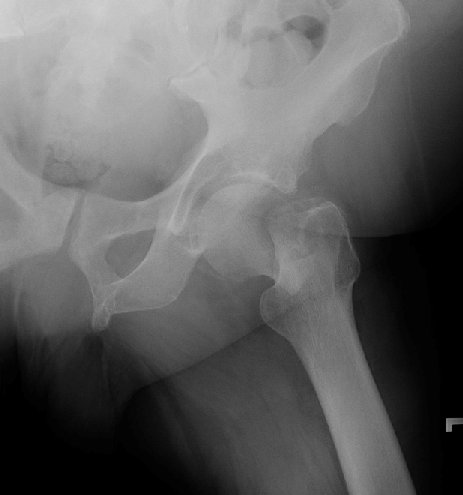

Return to Pathologic Fracture (Femur)